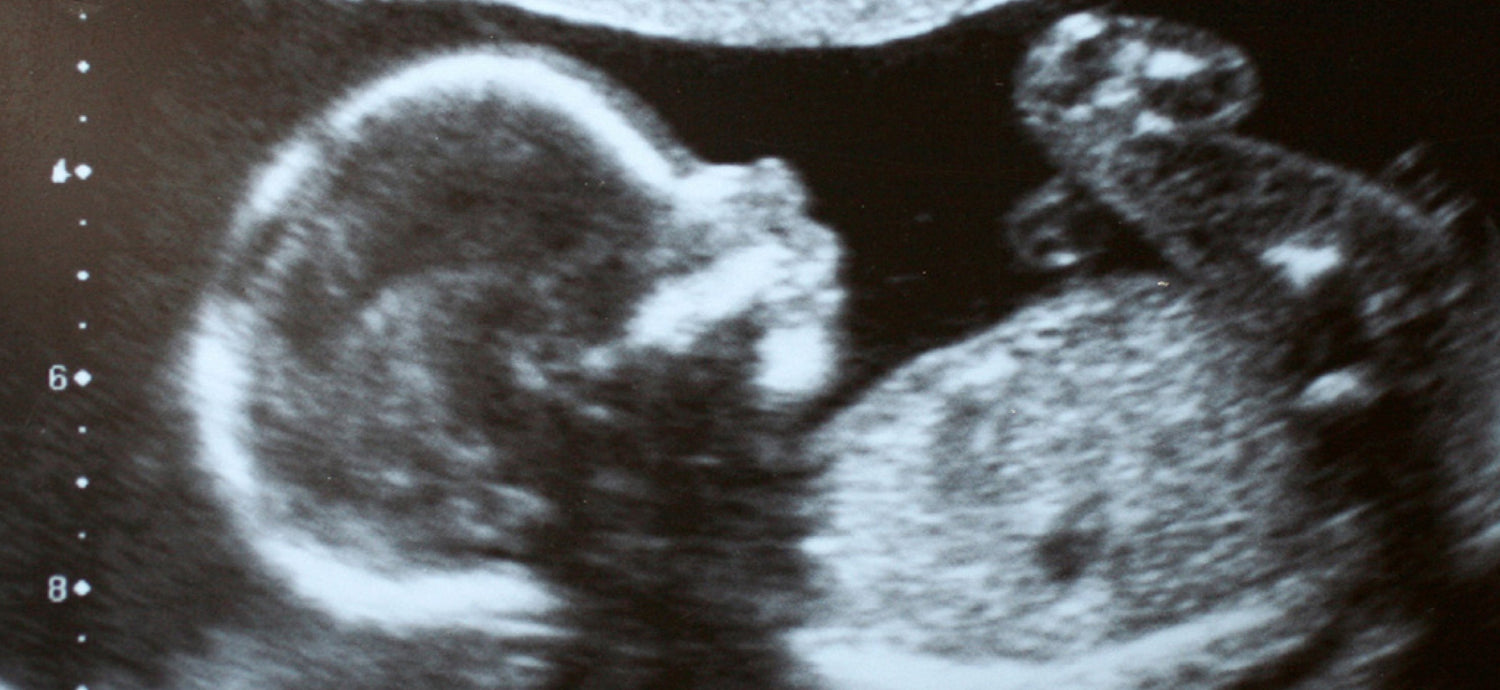

A baby's sense of taste begins to form at 8 weeks' gestation, when a cluster of receptors begin to form where their tongue will be and nerve cells are beginning to connect to the brain from different areas of the body. These receptors in the mouth eventually become tastebuds and when the neurological connections are made begin to recognise taste sensations like sweet, salty, bitter and sour.

Amniotic fluid can be “flavoured” because by the second trimester of pregnancy, a foetus is able to swallow amniotic fluid (a near-term foetus can swallow up to 1000 ml of amniotic fluid per day, which is about 50% of the entire volume of fluid in the sac!) This swallowing helps to regulate the amount of fluid in the amniotic sac and can assist with the development of the baby’s digestive and respiratory systems, as well as giving the fluid a distinct flavour and odour, depending on mums diet. Around week 16 is when the taste pores are developed and as the fluid flows across the tongue on the way to the baby’s digestive system, molecules in the fluid will interact with the taste buds, and your baby will experience the sensation of taste.